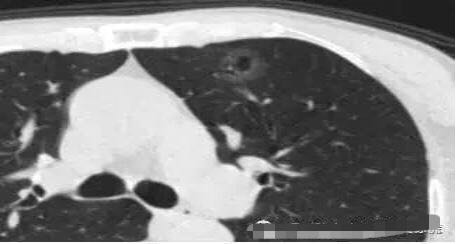

病例2

随访3年,GGO直径基本没有变化

2013年12月

2014年7月

2015年5月

2016年10月